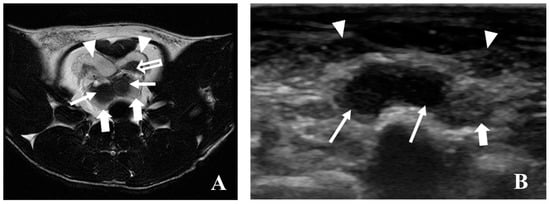

5.3. Magnetic Resonance Imaging (MRI)